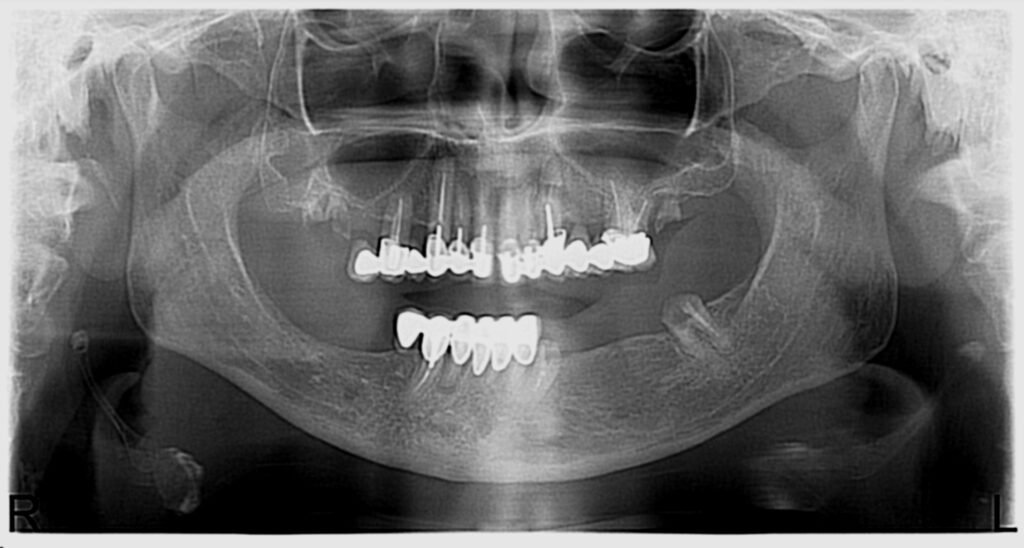

Réhabilitation complète mandibulaire : 4 implants et mise en charge immédiate

Patiente présentant une édentation mandibulaire nécessitant une réhabilitation complète implanto-portée.

Le plan de traitement a consisté en la pose de 4 implants au niveau de la mâchoire inférieure avec mise en charge immédiate, permettant une restauration fonctionnelle et esthétique rapide.

La réhabilitation finale a été réalisée par un bridge complet vissé, garantissant stabilité, confort et maintenance facilitée.